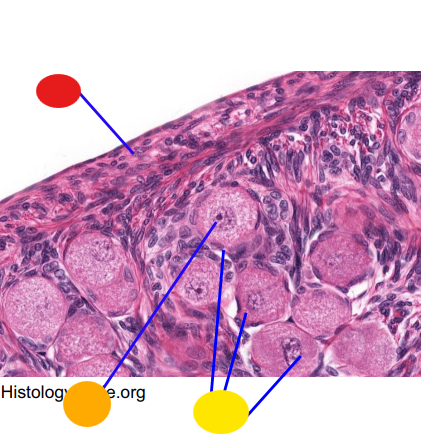

red

granulosa cells

orange

primary or secondary oocyte

yellow

oocyte nucleus

light green

zona pellucida

dark green

cumulus oophorus

light blue

antrum

dark blue

thecal cells

what is this

tertiary follicle

red

granulosa cells

orange

thecal cells

yellow

primary or secondary oocyte

light green

cumulus oophorus

dark green

antrum

what is this

tertiary follicle

what is this

secondary follicle

what is this

tertiary follicle

what is this

tertiary follicle